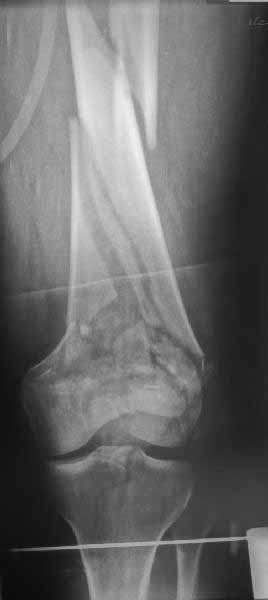

Рационально ориентироваться на качественный аспект - проблема или решается, или нет. Переломы типа 33C1 или C2 (то есть без фронтального раскалывания мыщелков, как на показанной Вами томограмме) при обычном качестве кости успешно можно фиксировать гвоздями с фронтальными винтами. Получается, их прочностных характеристик уже достаточно.

В приложении пример недавней операции, C3, открытая репозиция, фиксация мыщелков спицами и винтами, ретроградный синтез большеберцовым гвоздем 10,5 мм диаметром, винты 5 мм.

Но практика показывает, что классификации существуют не зря, и стоит пользоваться ими, а не ориентироваться на абстрактные "максимально низкие переломы". Подавляющее большинство поступающих к нам больных с дистальными переломами - это C1 и С2. И показанный в прошлом сообщении гвоздик прекрасно справляется. Наверно, сгодятся и многие современные гвозди разных производителей, типа RAFN Synthes. А вот при настоящих C3 одним гвоздем не обойтись, нужны как минимум винты мимо, а то и введение на одном уровне нескольких винтов и/или спиц веером...